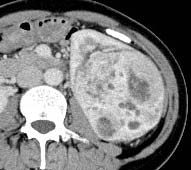

But, when we analyzed the degree of enhancement (hyperdensity, isodensity, hypodensity) in arterial (corticomedullary) and venous (nephrographic) phases showed significant difference. In arterial phase, most of clear cell RCC (21 of 39, 53.8%) showed hyperdensity, whereas none of non -ccRCC (0 of 22,0%) showed hyperdensity. The P value was 0 (P<0.05). In venous phase, ccRCC showed more hyperdensity or isodensity (9 and 4 0f 39, 23.1% and 10.3% respectively) than non-ccRCC (0 and 1 of 22, 0% and 4.5% respectively). Almost all of the non-clear cell RCC ( 21 However, we did not get any significant difference, when compared degree of enhancement in delayed phase (excretory phase). Table 3: shows the comparison of degree of enhancement in different phases in between ccRCC and non-ccRCC. The pattern of enhancement (homogeneous or heterogeneous) showed significant difference. Nonclear cell carcinoma (19 of 22, 86%) showed more heterogeneous enhancement pattern than that of clear cell carcinoma (21 of 39,53%). The P value was 0.012 (p<0.05).

However, when we compared pattern of enhancement, most of clear cell RCC (53.5%) showed heterogeneity, which agree with other studies related with pattern of enhancement of ccRCC [8,10]. But, when we made comparison of heterogeneity in between ccRCC and non-ccRCC, we found that, non-ccRCC were more heterogeneous than ccRCC. This may be because of larger size of non-ccRCC S which tended to show heterogeneity due to propensity of hemorrhage, necrosis and calcification [24][25][26]. At microscopic examination, all tumors with homogeneous enhancement were mainly composed of solid elements, whereas all tumors with heterogeneous enhancement had solid elements, necrosis, hemorrhage and calcifications.

In this study, we also made comparison in between ccRCC which showed hypovascularity and non-ccRCC. The number of ccRCC with hypovascularity was 8. Non-ccRCC (86.4%) were more heterogeneous than hypovascular ccRCC(25%). We also found that, necrosis was more common in non-ccRCC (81.8%) than hypovascular ccRCC(25%) and involvement of pelvis was more common in non-ccRCC(9.15%) than hypovascular ccRCC(0%). Hypovascular ccRCC (50%) showed predilection for involvement of medulla and most of non-ccRCC(90.9%) did not show any specific predilection for involvement of cortex, medulla and pelvis, rather than they showed involvement of more than one layer(mixed involvement).